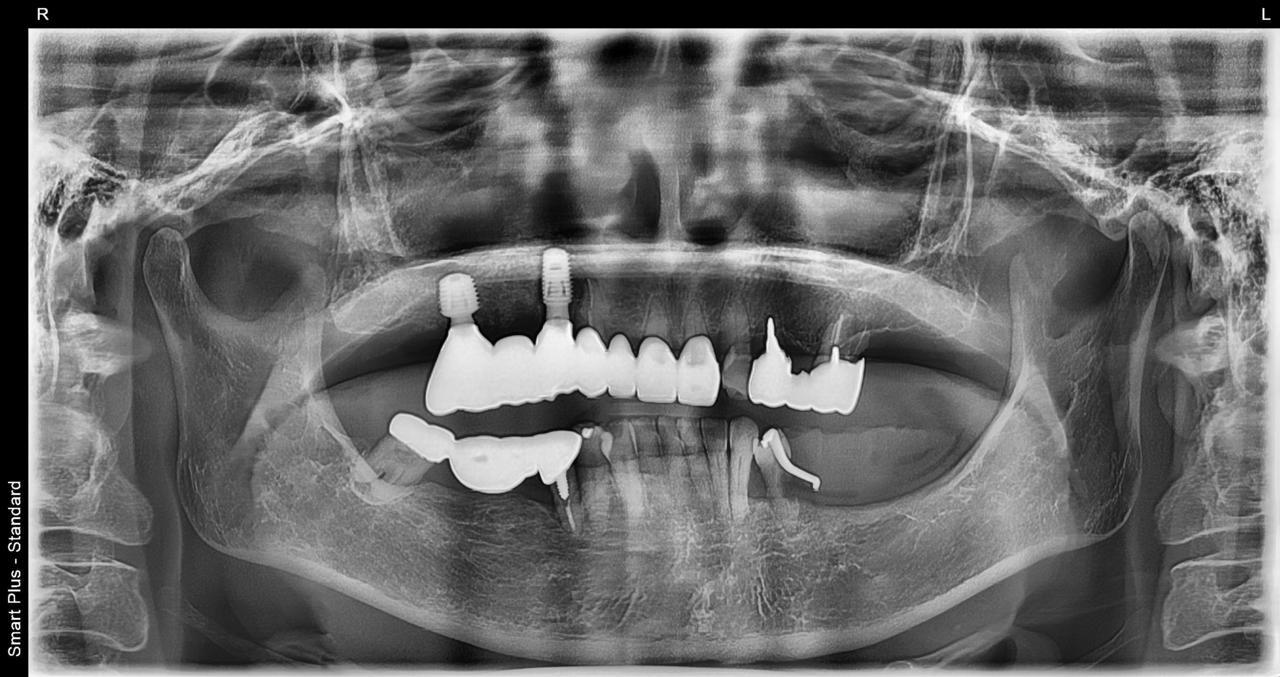

4.右上4~7番が重度に動揺しているために、抜歯した当日にインプラントを埋入して、3か月で最終的な歯を完成させたケース

Before

枚方市のインプラントの症例

After

K・S様 女性 60代

症状としては、 右上4から7番までのすべての歯の著しい動揺があり、食事が困難であった。

治療法としては、患者様は、患者様が3か月以内の治療完了を望んでいたために、炎症が若干あったが、右上4から7番ぼすべての抜歯を行い、右上4番(抜歯即時埋入)、右上6番(上顎洞までの骨がほとんどないため、グラフトレスサイナスリフト施行)にインプラントを1回法で手術を終え、2か月半後にインプラントの状態が安定したために、3か月で上部構造の、右上456のジルコニアブリッジを装着して、治療を終えています。

治療結果としては、抜歯したと同時にインプラントを埋入することで、抜歯した穴が自然に治る過程で、インプラントの骨結合と組織の治癒が同時に行われるために、3か月という治療期間で治療を終了することができたことと、機能面・審美面でも回復を行うができた。また、右上6番に関しては、グラフトレスサイナスリフトを行うことで、従来のサイナスリフトに比べ、約9か月早く治療を終えることができました。

治療の期間・回数:約3か月、インプラント抜歯即時埋入から最終補綴物装着まで8回

治療の価格:792000円(税込)

治療費の内訳:インプラント基本料(フィックスチャー(メガジェンインプラントANYONE使用) 及び手術費用、投薬費用、レントゲン費用、インプラント上部費用(アバットメントおよびジルコニアクラウンの費用用)330000円×2 660000円(税込み)。オプション、抜歯即時埋入加算(人工骨費用を含まず)5500円×2 11000円(税込み)右上5ジル9コニアブリッジのポンテック費用 88000円 右上6グラフトレスサイナスリフト費用 33000円(税込み

治療のリスクや副作用:手術後に、痛みや腫れ、出血、合併症などを引き起こす可能性があります。噛む感覚がご自身の歯と異なる場合があります。見た目がご自身の歯と異なる場合があります。手術後にメインテナンスを継続しないと、インプラントが抜け落ちる可能性があります。